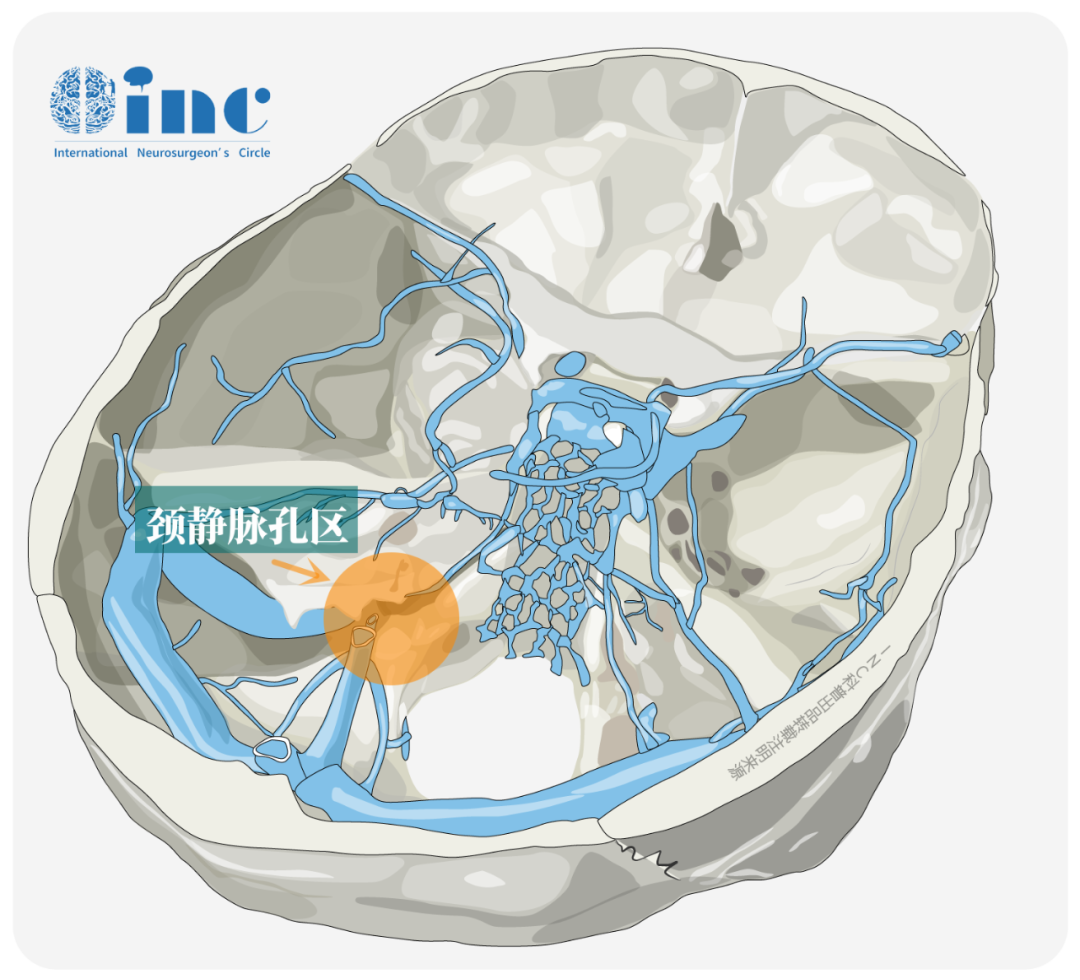

后组颅神经(舌咽神经、迷走神经和副神经)解剖结构复杂,在胚胎起源、走行特点和临床诊疗方面均具有显著的特殊性。这三对神经均起自延髓脑桥沟,其中舌咽神经源自第3咽弓,迷走神经来自第4和第6咽弓,副神经则由脑部(延续自迷走神经)和脊髓部(C5-6节段)共同组成。它们在延髓后外侧以多根细小的纤维束发出,经橄榄后沟走行,共同形成紧密交织的神经复合体,包裹于同一鞘膜内穿过颈静脉孔前内侧的神经部。在此复合体中,舌咽神经位置最靠前内侧且紧邻颈内动脉,具有独立的神经束膜包裹,而迷走神经和副神经则位于其后外侧。

这种精细的解剖结构使得后组颅神经在影像学上难以清晰辨识,成为诊断的难点。同时,由于该区域位置深在、毗邻重要血管神经、操作空间狭小,手术中极易造成损伤,是神经外科最具挑战性的区域之一。其复杂的解剖特点和重要的生理功能,使得后组颅神经的临床研究和诊疗工作始终是医学界的重点和难点领域。